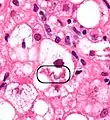

NASH (inflammation) and fibrosis stage 1

NASH (inflammation) and fibrosis stage 2

Lobular inflammation

The primary characteristic of NAFLD is the accumulation of lipids in the liver, largely in the form of triglycerides.[15] However, the mechanisms by which triglycerides accumulate and the reasons that accumulation can lead to liver dysfunction are complex and incompletely understood.[15][35][36][37] NAFLD can include steatosis along with varied signs of liver injury: either lobular or portal inflammation (a form of liver injury) or ballooning degeneration. Similarly, NASH can include histological features such as portal inflammation, polymorphonuclear cell infiltrates, Mallory bodies, apoptotic bodies, clear vacuolated nuclei, microvesicular steatosis, megamitochondria, and perisinusoidal fibrosis.[14] Hepatocyte death via apoptosis or necroptosis is increased in NASH compared with simple steatosis, and inflammation is a hallmark of NASH.[27]

NAFLD comprises two histological categories: NAFL, and the more aggressive form NASH. The presence of at least 5% fatty liver is common to both NAFL and NASH, but the features of substantial lobular inflammation and hepatocyte injuries such as ballooning or Mallory hyaline only occur in NASH. The majority of NAFL cases show minimal or no inflammation.[2][4][6] Pericentral and perisinusoidal fibrosis occur more often in adult-onset NASH, whereas portal fibrosis is more common in children with the disorder. NASH represents a more advanced stage of NAFL and is associated with poor outcomes such as cardiovascular events, cirrhosis, or hepatocellular carcinoma. ICD-11 does not use the term NAFL as it was deemed confusing with the family of disorders NAFLD. The preferred descriptions are instead: NAFLD without NASH or simple steatosis and "NASH". Also, the modifier with or without fibrosis or cirrhosis completes the diagnostic description.[2][6]